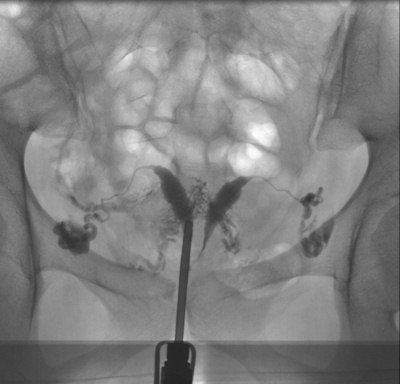

A 35-year-old patient with an irregular-shaped defect localized at the right side of the cervix, which was identified as a myoma using transvaginal sonography. No tubal pathology. No follow-up information was available for this external patient. All images courtesy of Dr. Adrian Schankath.Patients were identified by searching the institution's RIS for all HSG exams from September 2006 to April 2010. A total of 411 HSG exams were included in their study, with patients ranging in age from 22 to 42 years.